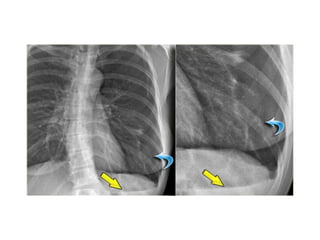

pleura

• The retracted visceral pleura is seen (blue arrow)

which indicates that there is a pneumothorax.

• There is a horizontal line visible (yellow arrow).

Normally there are no straight lines in the human

body unless when there is an air-fluid level.

This means that there is a hydro-pneumothorax.

• When a pneumothorax is small, this air-fluid level

can be the only key to the diagnosis of a

pneumothorax.

pleura • The retractedvisceral pleura is seen (blue arrow) which indicates that there is a pneumothorax. • There is a horizontal line visible (yellow arrow). Normally there are no straight lines in the human body unless when there is an air-fluid level. This means that there is a hydro-pneumothorax. • When a pneumothorax is small, this air-fluid level can be the only key to the diagnosis of a pneumothorax.